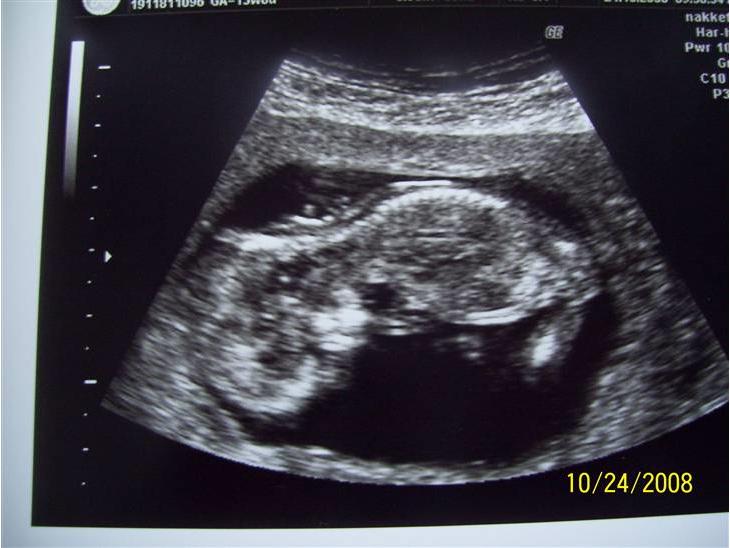

Her er billeder af vores lille baby i maven, vi håber at alt er okay da vi desværre fik et NF tal på 217

Scannings billeder 12+4